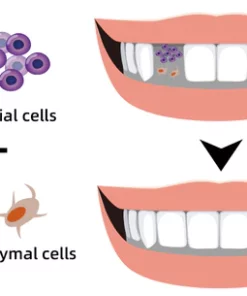

Stimulate The Regrowth Of Lost Teeth

FURZERO™ Herbal Brightening Oral Repair Foam can stimulate the gum bone to produce epithelial cells and mesenchymal cells, which will form new tooth germs and grow new teeth. It is a perfect solution for accidental tooth loss, tooth loss due to necrosis, and elderly tooth loss. No need to go to the dentist for expensive dentures.